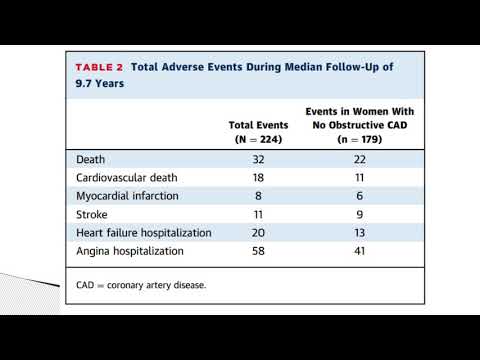

Impacto de la reactividad coronaria anormal a largo plazo en mujeres. Dr. Mariano Napoli Llobera. Residencia de Cardiología. Hospital C. Argerich. Buenos Aires